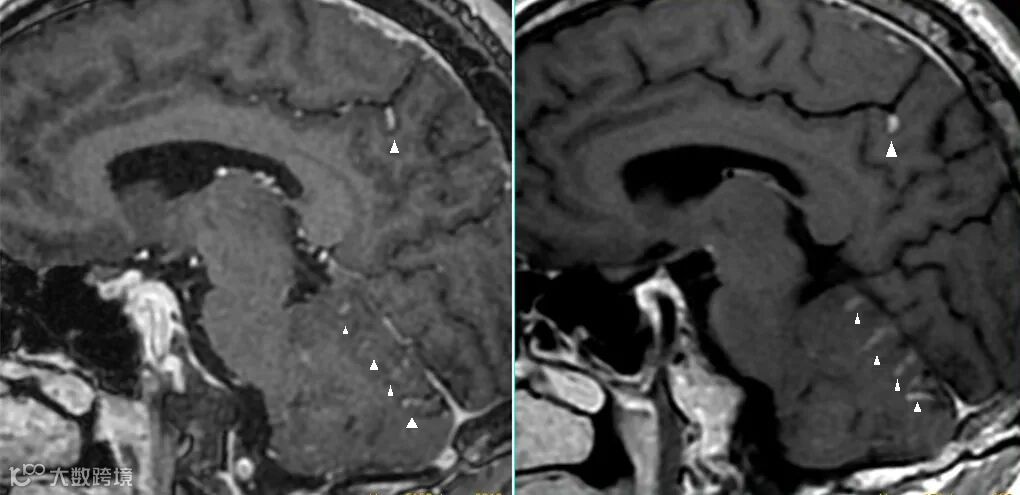

但该序列上血管同样会呈现为高信号,并不利于血管与强化病灶间的鉴别。在3D T1梯度回波序列上血管呈高信号,并不利于与强化病灶的鉴别诊断,如上图△左所示病灶可能会被误认为血管信号。 -

该序列虽然灰白质对比度不及磁化准备的3D T1梯度回波序列,但其增强后快速流动的血液呈现为低信号的“黑血”表现,更有利于血管与强化病灶间的鉴别。 -

如上一病例;图△左为3D T1磁化准备梯度回波序列,图右为3D可变翻转角的T1 自旋回波序列。